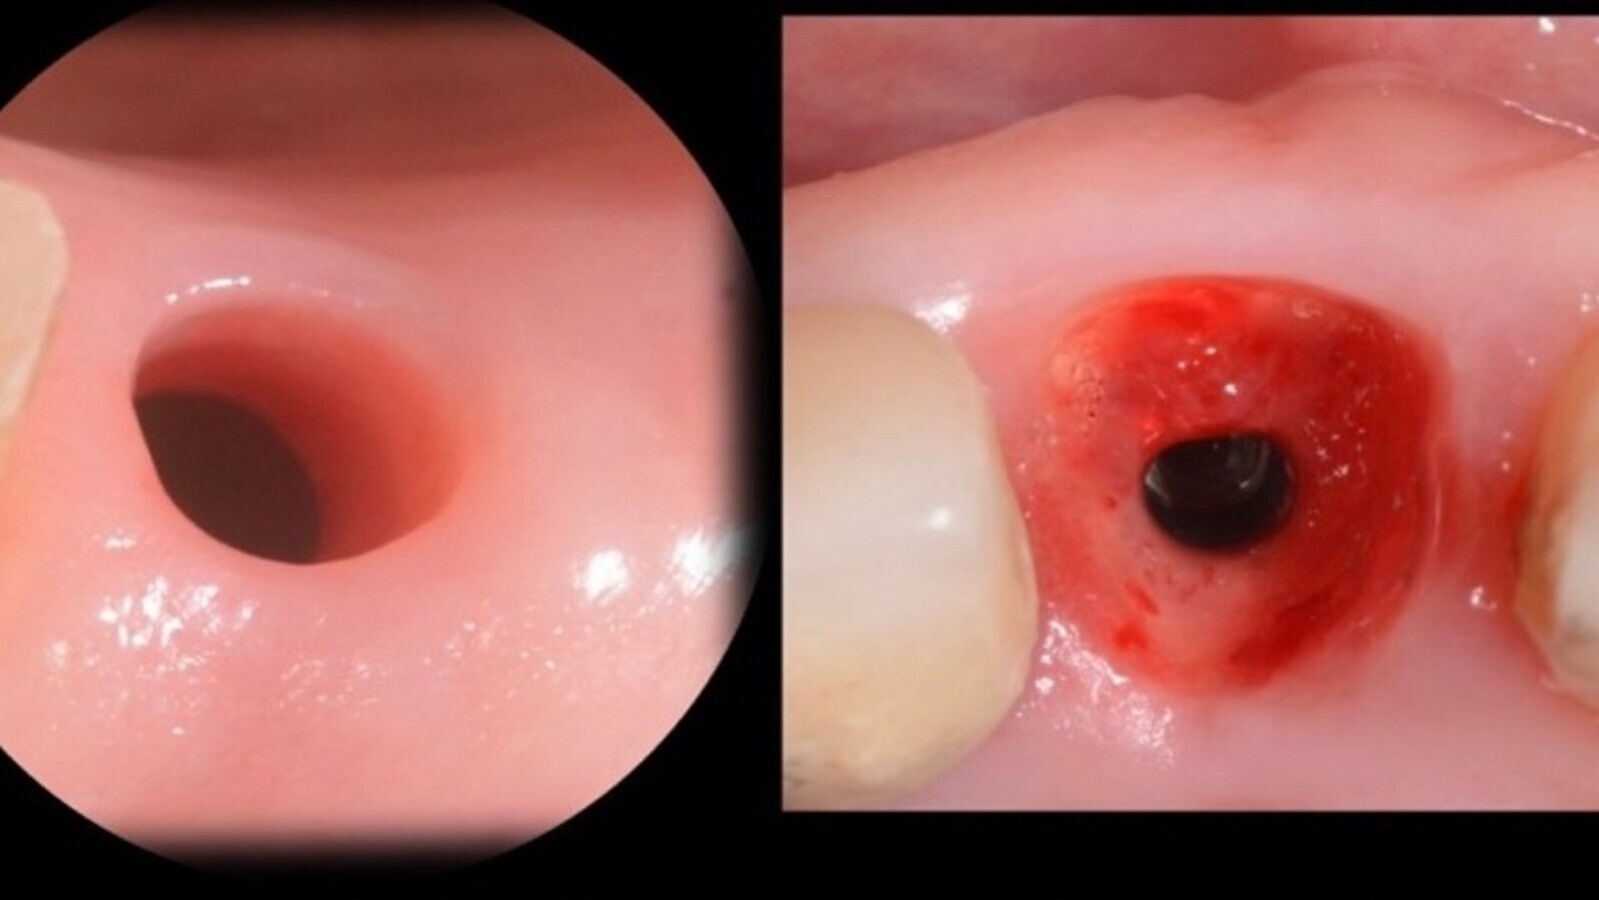

Fig. 6. Comparación entre un implante con tapa cicatrizal y otro con Sculgar (Imagen gentileza de NTI).

Fig. 9. Perfil de emergencia comparando estado gingival con tapa cicatrizal y con Sculgar (Imagen gentileza de NTI).